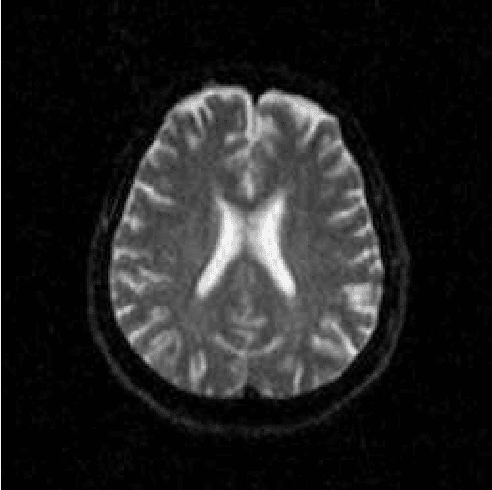

Abstract:Alzheimer's disease is the most common cause of dementia, yet difficult to accurately diagnose without the use of invasive techniques, particularly at the beginning of the disease. This work addresses the classification and analysis of multispectral synthetic images composed by diffusion-weighted magnetic resonance brain volumes for evaluation of the area of cerebrospinal fluid and its correlation with the progression of Alzheimer's disease. A 1.5 T MR imaging system was used to acquire all the images presented. The classification methods are based on multilayer perceptrons and classifiers of radial basis function networks. It is assumed that the classes of interest can be separated by hyperquadrics. A polynomial network of degree 2 is used to classify the original volumes, generating a ground-truth volume. The classification results are used to improve the usual analysis by the map of apparent diffusion coefficients.

Abstract:Multispectral image analysis is a relatively promising field of research with applications in several areas, such as medical imaging and satellite monitoring. A considerable number of current methods of analysis are based on parametric statistics. Alternatively, some methods in Computational Intelligence are inspired by biology and other sciences. Here we claim that Philosophy can be also considered as a source of inspiration. This work proposes the Objective Dialectical Method (ODM): a method for classification based on the Philosophy of Praxis. ODM is instrumental in assembling evolvable mathematical tools to analyze multispectral images. In the case study described in this paper, multispectral images are composed of diffusion-weighted (DW) magnetic resonance (MR) images. The results are compared to ground-truth images produced by polynomial networks using a morphological similarity index. The classification results are used to improve the usual analysis of the apparent diffusion coefficient map. Such results proved that gray and white matter can be distinguished in DW-MR multispectral analysis and, consequently, DW-MR images can also be used to furnish anatomical information.

Abstract:The unsupervised classification has a very important role in the analysis of multispectral images, given its ability to assist the extraction of a priori knowledge of images. Algorithms like k-means and fuzzy c-means has long been used in this task. Computational Intelligence has proven to be an important field to assist in building classifiers optimized according to the quality of the grouping of classes and the evaluation of the quality of vector quantization. Several studies have shown that Philosophy, especially the Dialectical Method, has served as an important inspiration for the construction of new computational methods. This paper presents an evaluation of four methods based on the Dialectics: the Objective Dialectical Classifier and the Dialectical Optimization Method adapted to build a version of k-means with optimal quality indices; each of them is presented in two versions: a canonical version and another version obtained by applying the Principle of Maximum Entropy. These methods were compared to k-means, fuzzy c-means and Kohonen's self-organizing maps. The results showed that the methods based on Dialectics are robust to noise, and quantization can achieve results as good as those obtained with the Kohonen map, considered an optimal quantizer.

Abstract:The materialist dialectical method is a philosophical investigative method to analyze aspects of reality. These aspects are viewed as complex processes composed by basic units named poles, which interact with each other. Dialectics has experienced considerable progress in the 19th century, with Hegel's dialectics and, in the 20th century, with the works of Marx, Engels, and Gramsci, in Philosophy and Economics. The movement of poles through their contradictions is viewed as a dynamic process with intertwined phases of evolution and revolutionary crisis. In order to build a computational process based on dialectics, the interaction between poles can be modeled using fuzzy membership functions. Based on this assumption, we introduce the Objective Dialectical Classifier (ODC), a non-supervised map for classification based on materialist dialectics and designed as an extension of fuzzy c-means classifier. As a case study, we used ODC to classify 181 magnetic resonance synthetic multispectral images composed by proton density, $T_1$- and $T_2$-weighted synthetic brain images. Comparing ODC to k-means, fuzzy c-means, and Kohonen's self-organized maps, concerning with image fidelity indexes as estimatives of quantization distortion, we proved that ODC can reach almost the same quantization performance as optimal non-supervised classifiers like Kohonen's self-organized maps.

Abstract:Alzheimer's disease is the most common cause of dementia, yet hard to diagnose precisely without invasive techniques, particularly at the onset of the disease. This work approaches image analysis and classification of synthetic multispectral images composed by diffusion-weighted magnetic resonance (MR) cerebral images for the evaluation of cerebrospinal fluid area and measuring the advance of Alzheimer's disease. A clinical 1.5 T MR imaging system was used to acquire all images presented. The classification methods are based on multilayer perceptrons and Kohonen Self-Organized Map classifiers. We assume the classes of interest can be separated by hyperquadrics. Therefore, a 2-degree polynomial network is used to classify the original image, generating the ground truth image. The classification results are used to improve the usual analysis of the apparent diffusion coefficient map.